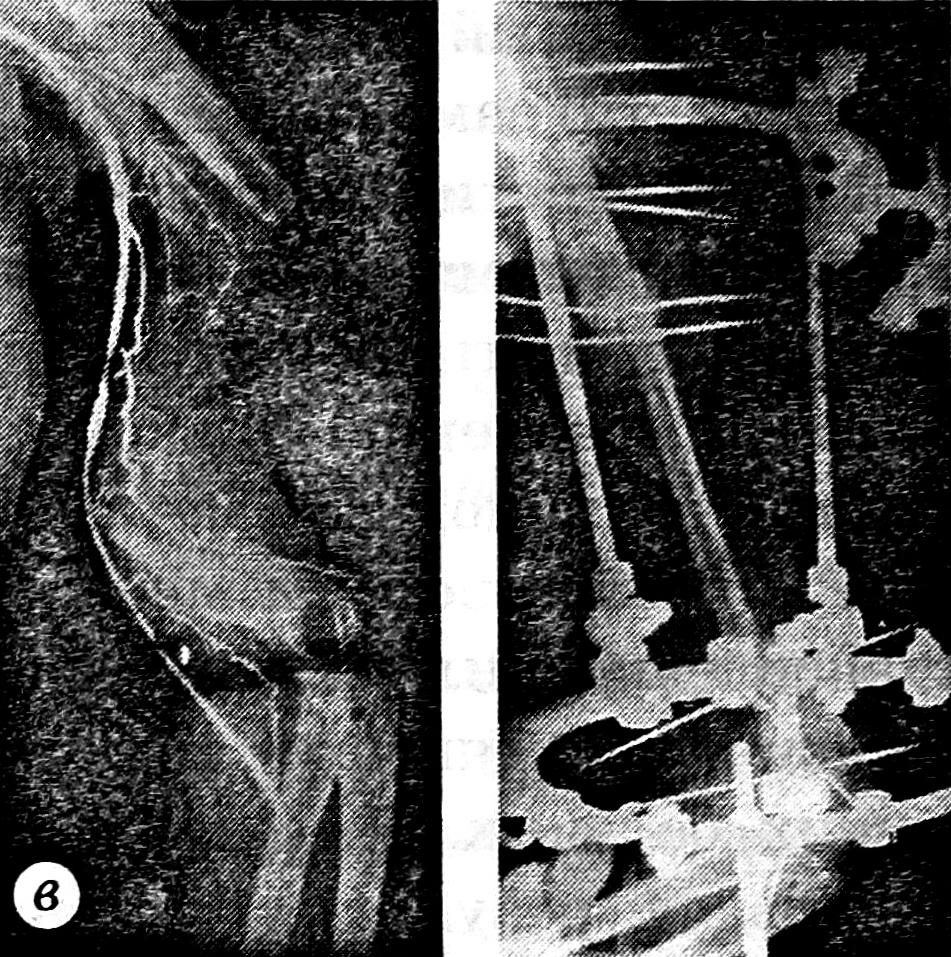

28.04.87 больной произведена аутопластика дефекта левой плечевой кости свободным васкуляризованным аутотрансплантатом из правой малоберцовой кости с одновременной транспозицией широчайшей мышцы спины на переднюю поверхность плеча с целью воссоздания кожного покрова и восстановления активного сгибания в локтевом суставе. Сосуды костного трансплантата анастомозированы с плечевой артерией конец в бок, трансплантат внедрен интрамедуллярно в концы реципиентной кости, произведен остеосинтез аппаратом Илизарова (рис. 2 и 3).

Рис. 2. Дефект плечевой кости восполнен свободным васкуляризованным малоберцовым аутотрансплантатом, произведен остеосинтез в аппарате Илизарова.

Рис. 3. Спланирован торакодорсальный лоскут для транспозиции на переднюю поверхность плеча (а), широчайшая мышца спины перемещена на плечо, восполнен дефект кожного покрова (б).

Рис. 4. Через 3 мес после операции: полная консолидация трансплантата с реципиентной костью.